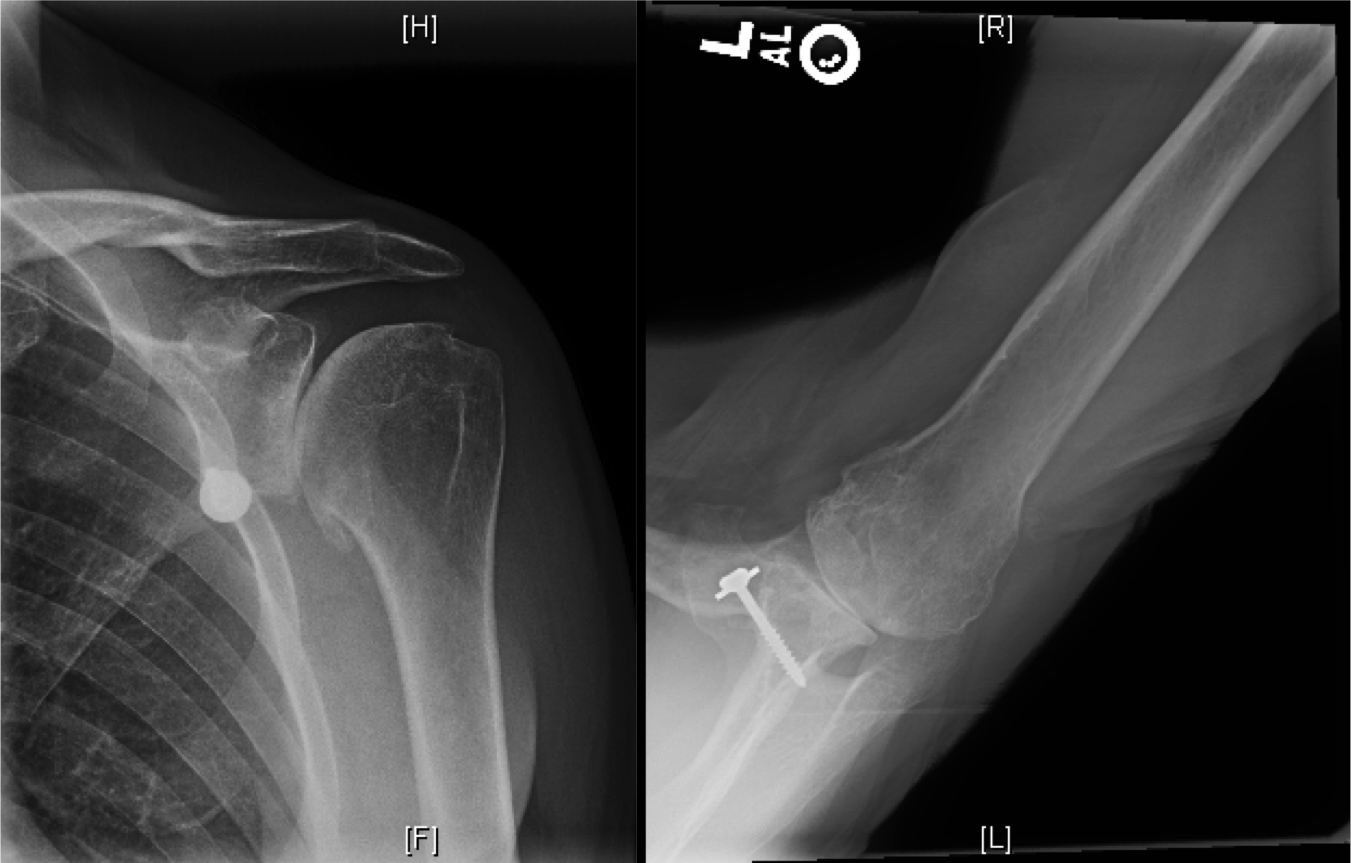

rotator cuff syndrome encompasses various injuries or degenerative conditions affecting the rotator cuff, such as subacromial. the most common indications for shoulder arthroplasty are pain from shoulder arthritis with a loss of function that is unresponsive to. rcta has three major characteristics: with so many moving parts and so many ways to damage those parts, coding injuries to the rotator cuff isn’t always straightforward. m12.811 is a billable diagnosis code used to specify a medical diagnosis of other specific arthropathies, not elsewhere classified,. rcta has three major characteristics: First, massive rotator cuff tear (fig. rotator cuff tear arthropathy is a spectrum of degenerative disease that develops due to a rotator cuff deficient. rotator cuff arthropathy is a specific pattern of shoulder degenerative joint disease that results from a rotator cuff tear leading to. M75.122 complete rotator cuff tear.

Rotator Cuff Arthropathy Shoulder Icd 10 M75.122 complete rotator cuff tear. M75.122 complete rotator cuff tear. rotator cuff syndrome encompasses various injuries or degenerative conditions affecting the rotator cuff, such as subacromial. M75.121 complete rotator cuff tear or rupture right shoulder, not specified as traumatic. disabling cuff tear arthropathy (cta) is commonly managed with reverse shoulder arthroplasty (rsa). rcta has three major characteristics: Bilateral rotator cuff arthropathy of. • new patterns such as. rcta has three major characteristics: with so many moving parts and so many ways to damage those parts, coding injuries to the rotator cuff isn’t always straightforward. • there is no universally accepted classification for rc tears. the most common indications for shoulder arthroplasty are pain from shoulder arthritis with a loss of function that is unresponsive to. m12.811 is a billable diagnosis code used to specify a medical diagnosis of other specific arthropathies, not elsewhere classified,. m75.121 is a billable diagnosis code used to specify a medical diagnosis of complete rotator cuff tear or rupture of right. First, massive rotator cuff tear (fig. rotator cuff tear arthropathy is a spectrum of degenerative disease that develops due to a rotator cuff deficient.